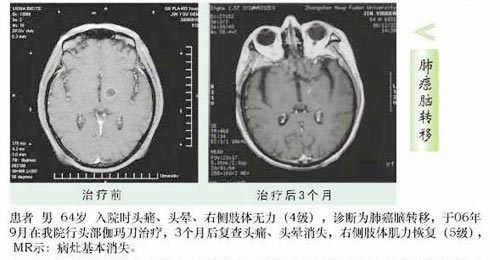

肺癌最常见的远处转移部位之一是脑部。 肺癌脑转移 患者预后差,自然平均生存时间仅1个月-2个月。肺癌脑转移的治疗已经成为临床关注的热点之一。脑膜转移患者的临床表现常因肿瘤细胞侵犯部位不同而复杂多样,缺乏特异性,有时很难与脑实质转移引起的症状 ...